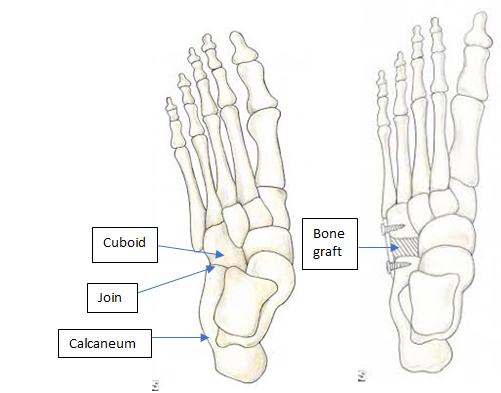

Flat feet british army new arrivals